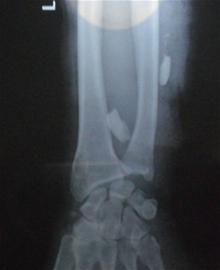

記者趕到401醫(yī)院時(shí),醫(yī)生正在為受傷老人做檢查。記者發(fā)現(xiàn)老人左前臂纏上了厚厚的紗布,而且手腕處的傷口鮮血還不斷往外滲,醫(yī)生用繃帶將傷臂吊在脖子上。老人的右胳膊也有傷口,手腕處纏了厚厚的繃帶。此外,老人的雙手多處劃傷,滿是暗紅色的血漬。醫(yī)生在檢查的過程中,老人家屬向醫(yī)生出示了在當(dāng)?shù)蒯t(yī)院拍攝的X光片,通過X光片可以清晰地看到插入胳膊中的兩顆豬牙。醫(yī)護(hù)人員診斷后將老人送到手術(shù)室準(zhǔn)備手術(shù)。